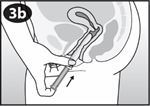

Betrachten Sie die Abbildung des Applikators um sich mit den Komponenten des Applikators vertraut zu machen. |

Ziehen Sie den Kolben behutsam bis zum Anschlag heraus. |

Drücken Sie die gegenüberliegenden Seiten des Vaginalrings zusammen und führen Sie den Vaginalring in die Gehäuseöffnung ein. |

Drücken Sie den Vaginalring behutsam in das Gehäuse. Die Spitze des Vaginalrings sollte ein wenig aus der Gehäuseöffnung herausragen. |

Fassen Sie mit Daumen und Mittelfinger den Griffbereich. |

Führen Sie das Gehäuse behutsam in die Scheide ein, bis Ihre Finger (auf dem Griffbereich) Ihren Körper berühren. |

Der Vaginalring wird aus dem Applikator gedrückt. Entfernen Sie den Applikator behutsam. |